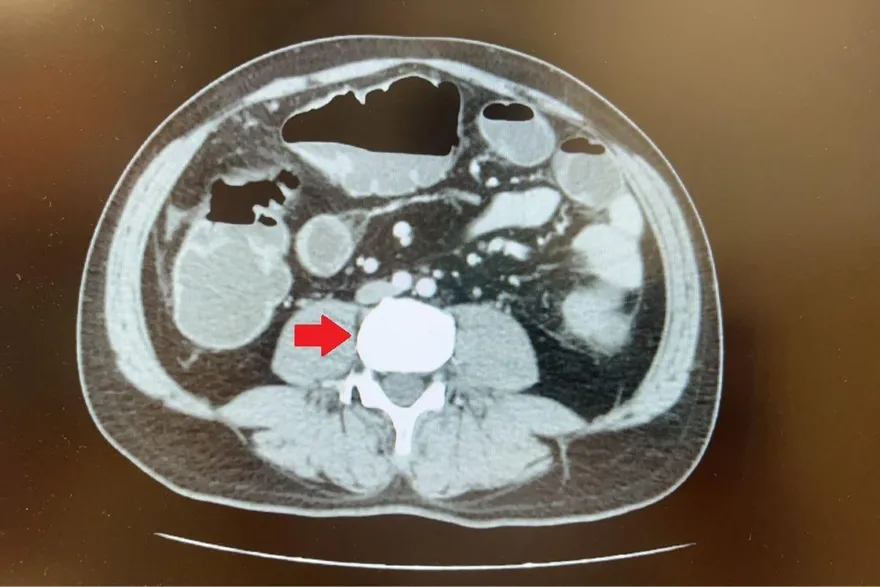

腸套疊

Vanek腫瘤

小腸套疊

發炎性纖維類息肉

腹腔鏡手術

平等澄清醫院

腸道疾病

良性腫瘤

小腸腫瘤

腹部疼痛